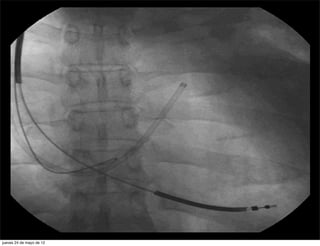

electrodo en su puesto

electrodo en supuesto jueves 24 de mayo de 12